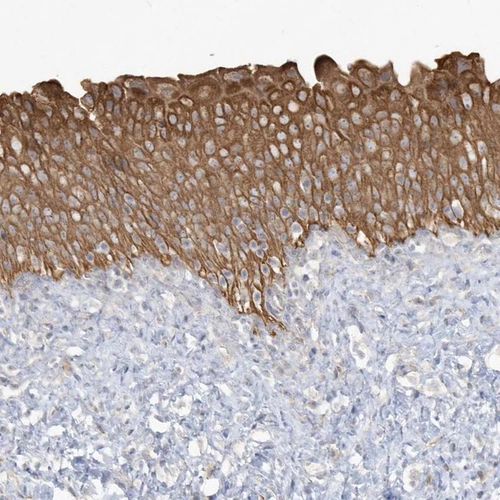

Immunohistochemical staining of human urinary bladder shows strong cytoplasmic positivity in urothelial cells.